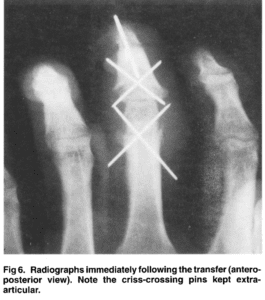

homodigital island transfer

Distal interphalangeal joint to proximal interphalangeal joint homodigital island transfer…

Fixation method for unstable bony mallet finger

A simple fixation method for unstable bony mallet finger A…